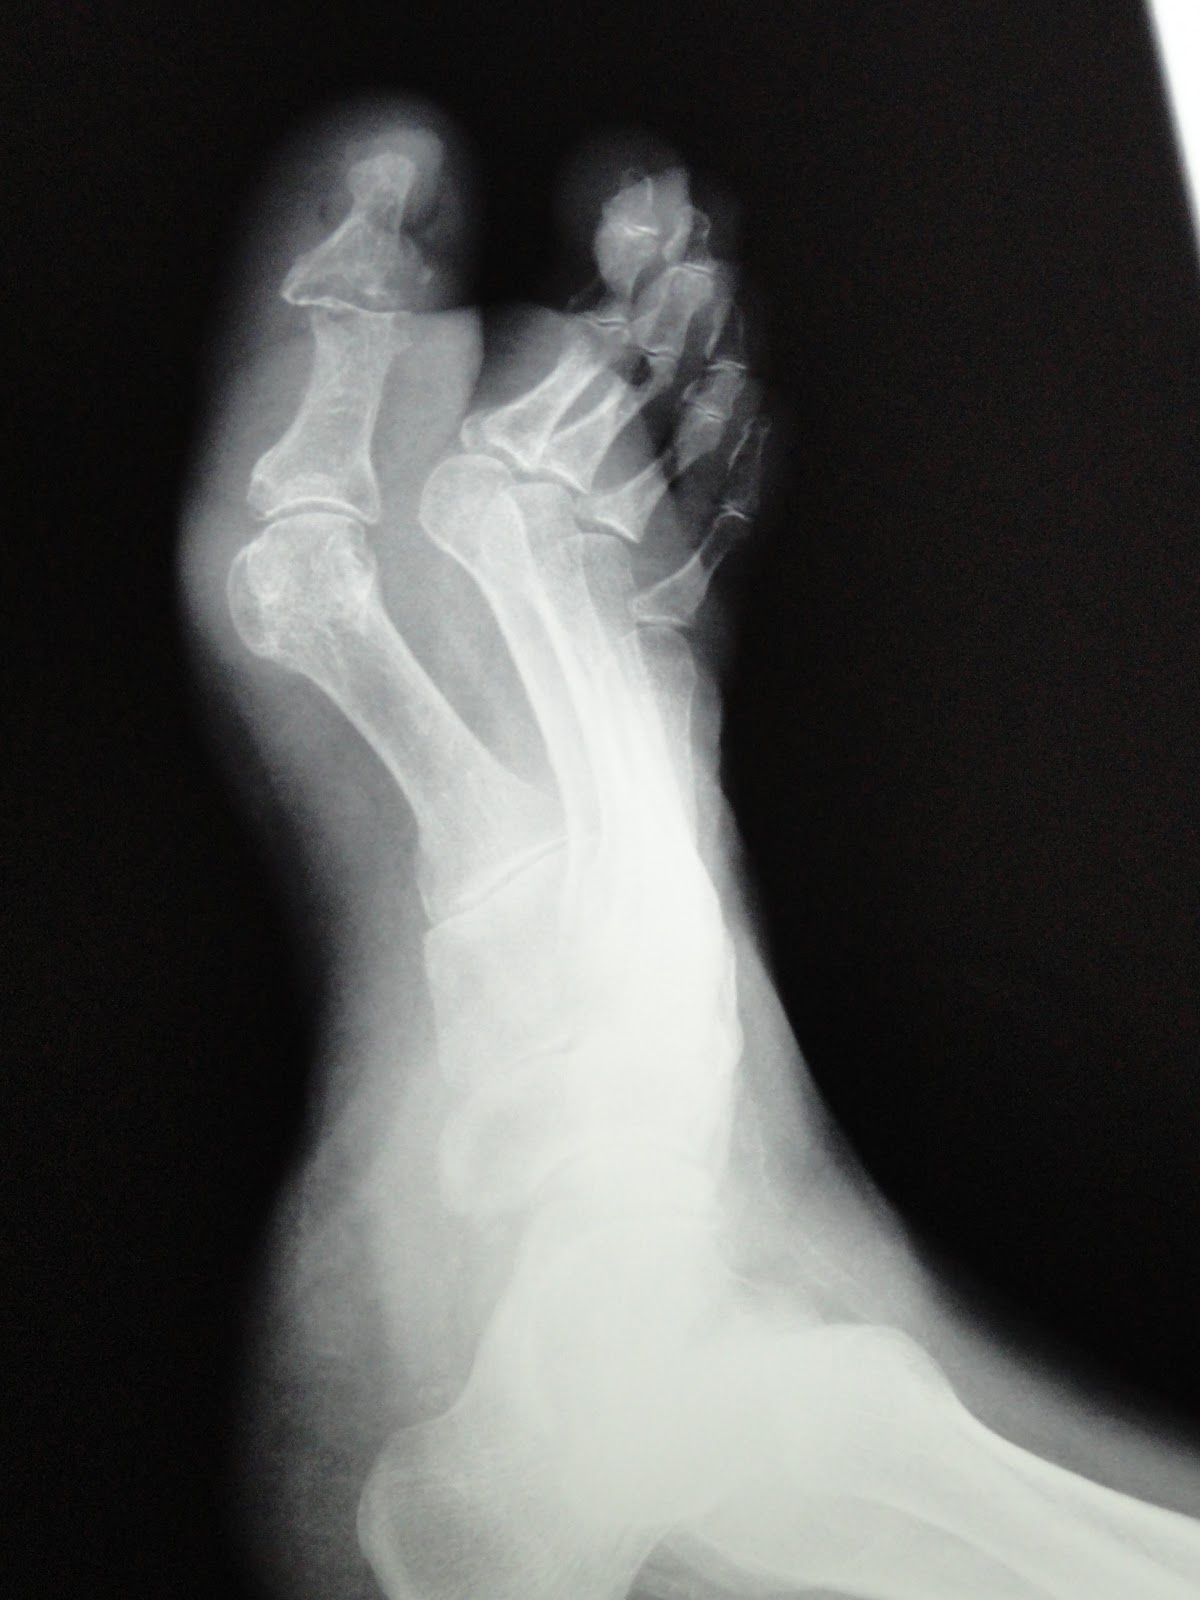

EVOLUCION PIE DIABETICO MAS OSTEOMIELITIS POR S. AUREUS.